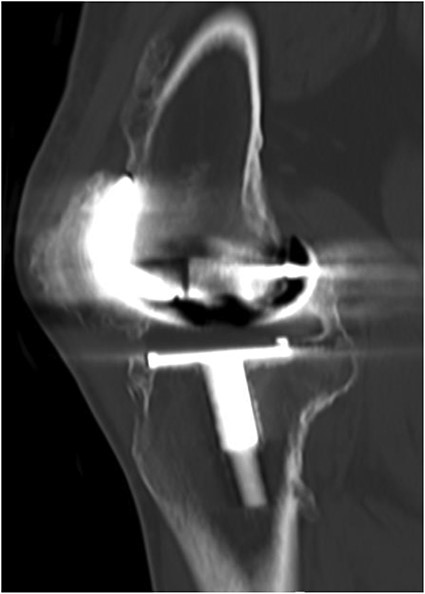

A 32-year-old female known case of rheumatoid arthritis affecting both knees presented to our clinic complaining of severe right knee stiffness post TKA 4-years-ago done in an outside facility (Figs. 1 and 2). She lives in a rural community and was on hydroxychloroquine, but her disease was active as she was not compliant to her medication. On physical examinations, the right knee was larger in size compared to the left knee without joint effusion. Range of motion was zero on flexion, −10° in extension. Standing knee X-ray showed HO around the prosthesis (Fig. 2). Computed tomography (CT) demonstrated extensive HO with implants fixed in place (Fig. 3). Revision surgery and replacement of the prostheses was considered to restore function.

CT demonstrated extensive heterotopic ossification involving the popliteal fossa, the anterior surface of the patella and at the distal third of anterior femur extending to the level of the knee-replacement prosthesis. There was no evidence of implant looseness or alignment deformity and there was no evidence of progressive ossification.